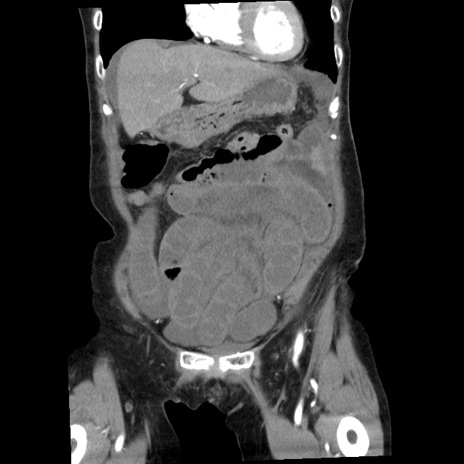

症例1(冠状断像)

【症例】80歳代女性

【主訴】腹痛

【現病歴】8時間前から腹痛あり来院。

【既往歴】糖尿病、脂質異常症、子宮体癌にて子宮全摘術

【身体所見】意識清明・会話良好だが腹痛で苦悶様、全腹部にわたって反跳痛と圧痛あり

【データ】WBC 13600、CRP 0.14、LDH 224、CK 90